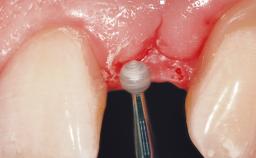

Implant Placement with Simultaneous Contour Augmentation using GBR

Surgical treatment of a 67-year-old male patient exhibiting an extended edentulous space in the anterior maxilla after the removal of three hopeless incisor teeth.

The video demonstrates implant placement using a surgical stent according to the principle of prosthodontically driven implant placement. The deficient ridge is augmented with locally harvested autologous bone chips, a superficial layer of xenogenic DBBM particles and a resorbable collagen membrane. The surgery is completed with a precise, tension-free primary wound closure.